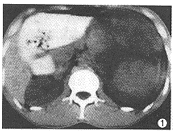

CT表现: 右肾上腺区一卵圆形囊状液性密度占位,CT值11.2HU,内有散在点状钙化,边缘 光整,囊壁后方与弧形受压的肾上腺实质相延续(图1);增强扫描囊内不强化,囊壁与肾上 腺均呈轻度强化(图2);下方的肾上极受压移位,轻度变形,但皮髓质完整(图3)。左前方的 胰头及上方的肝脏均为受压移位表现。

图1 CT平扫示右肾上腺区囊性占位,包膜光整,其内有多个点状钙化 图2 CT增强扫描示囊壁轻度强化,右肾上腺与囊肿关系密切(↑) 图3右肾受压、移位,但肾上极皮、髓质完整征[3]。而肝、肾囊肿内均极少出现钙化。对于一些极少见的 非典型肾上腺囊肿,由于囊内胶冻样物质CT值可达60HU左右[4],易误诊为肾上腺 的其他实性肿瘤,正确诊断需结合超声。